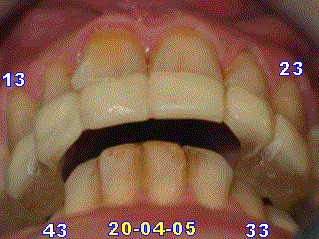

-dimension verticale: recouvrement d'un tiers en vue frontale de 31 41 par 11 21

- Pour rappel aux Confrères ODF qui ne connaîtraient pas l’Occlusodontologie (Jeanmonod A., Paris) : comme le montre les deux photos ci-jointes, l’Occlusodontologie ne se préoccupe jamais du recouvrement overjet / overbite, ni de la classe d’E. H. Angle, ni de (etc.), pour autant que la Relation maxillo-mandibulaire soit devenue MyoDéterminée Asymptomatique = « RMDA » qui rend le patient et le praticien heureux, puisque disparition de tous les signes (obj., praticien) et symptômes (subj., patient). Autrement dit, un traitement peut aboutir à une RMDA avec une canine inf. en occlusion « volontaire » et en occlusion « réflexe » sur une PM1 ou PM2 ou M1 supérieures, que cela ne perturbe que les références bibliographiques scientifiques et les préjugés, mais jamais le patient, ni le praticien Occlusodontologiste, puisque la RMDA est définitivement acquise = relation 100 % physiologique (Physiologie neuromusculaire) = patient en parfaite santé manducatrice = patient qui ne mérite aucun traitement supplémentaire puisqu’il se porte à merveille sans aucun symptôme et qu’il ne se plaint de rien. Quel praticien voudrait plus / quel dentiste oserait faire plus sur une précision des propriocepteurs comprise entre 0,001 et 0,02 mm ?